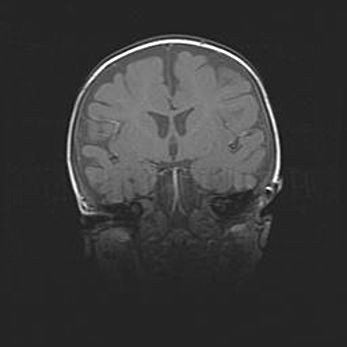

Сообщающаяся гидроцефалия. Кистозная энцефаломаляция головного мозга.

Возраст: 3 месяца 4 дня

Вес: 3100 г

Пол: женский

Окружность головы: 34 см

Срок гестации: 31 неделя

Кистозная энцефаломаляция головного мозга - одна из форм поражения головного мозга в детском возрасте. Характеризуется возникновением множественных и распространённых кист в коре, белом веществе и подкорковых образованиях головного мозга у плодов, новорождённых и детей раннего возраста. Развитие кистозной энцефаломаляции связано с внутриутробной асфиксией и гипотонией, родовой травмой, тромбозом синусов, пороками развития сосудов, инфекциями, сепсисом и другими причинами. Наиболее значимые инфекционные агенты: вирусы простого герпеса, цитомегалии, краснухи, токсоплазмы, энтеробактерии, золотистый стафилококк и другие.